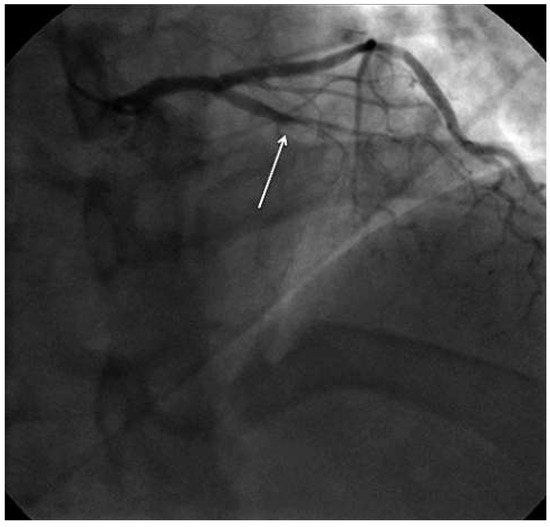

Interesting Images

Unusual Complication of Transradial Coronary Angiography

by Panneerselvam Arunkumar

Cardiovasc. Med. 2014, 17(2), 54; https://doi.org/10.4414/cvm.2014.00214 - 19 Feb 2014

Viewed by 133

Abstract

A 68-year-old male with diabetes and hypertension underwent a coronary angiogram, t hrough the right radial artery approach, because of inducible ischaemia on stress testing [...] Full article

Show Figures

Figure 1